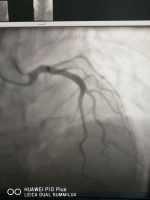

過度悲傷還是過于興奮?注意應(yīng)激性心臟病——心碎綜合癥 關(guān)鍵疾?。?a href="http://m.akellydesign.com/tags/so/應(yīng)激性心臟病-4-1.html" target="_blank">應(yīng)激性心臟病 現(xiàn)病史【一般資料】 女性,53歲,在職 【主訴】 發(fā)作性胸悶、氣喘4年,加重伴胸痛6小時(shí)。 【現(xiàn)病史】患者4年前開始出現(xiàn)發(fā)作性胸悶、氣短,多于勞累及情緒激動(dòng)時(shí)發(fā)作,休息可以逐漸緩解,無胸痛、肩背部放射痛,無咳嗽、咳痰、發(fā)熱,曾經(jīng)在我院診斷為冠心病,長期口服阿司匹林、消心痛等藥物治療,上述病情偶有發(fā)作?;颊呷朐呵?小時(shí)情緒激動(dòng)后出現(xiàn)胸悶、氣短加重,并且伴有明顯的胸痛,主要是胸骨后及心前區(qū)持續(xù)的鈍痛,含服硝酸甘油不能緩解,由于過度悲傷不能自主活動(dòng)。 【既往史】既往高血壓病是7年,血壓最高達(dá)到170/1...

董***芝 | 副主任醫(yī)師 內(nèi)科 心血管內(nèi)科 瀏覽:8716